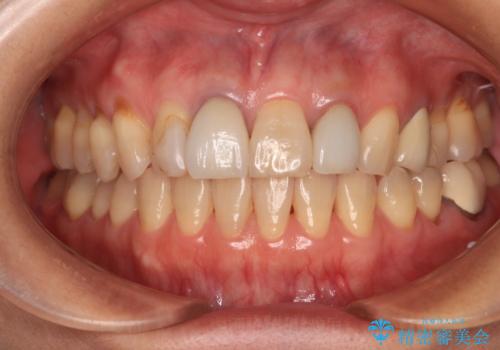

- 詰め物やクラウンで色合いが異なっている上顎前歯を気にして来院された患者様です。

長さや形を左右対称に整えたいとのことで、4歯をオールセラミッククラウンにて補綴治療を行うこととしました。